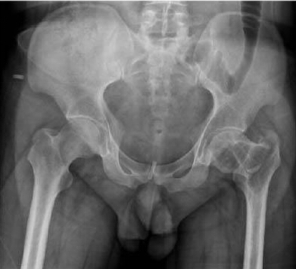

患者是一名23岁男性,因轻微暴力导致左侧股骨颈骨折,完善相关检查,明确诊断为股骨近端骨肉瘤伴病理性骨折。

骨肉瘤是最常见的原发性恶性骨肿瘤,好发于10-25岁青少年。骨肉瘤增殖能力强、进展迅速、易发生早期转移,患者的预后较差。考虑到患者年轻,切除肿瘤的同时如何保证患肢的功能成为了问题的关键。诊断明确后,科室专家在胡勇主任医师的带领下为患者定制了新辅助化疗为保障的保肢治疗方案。化疗后达到了安全的外科边界,3D打印手术模型,精准切除肿瘤,定制截骨导板和3D打印的髋臼为患者量身定制3D打印全髋关节假体。